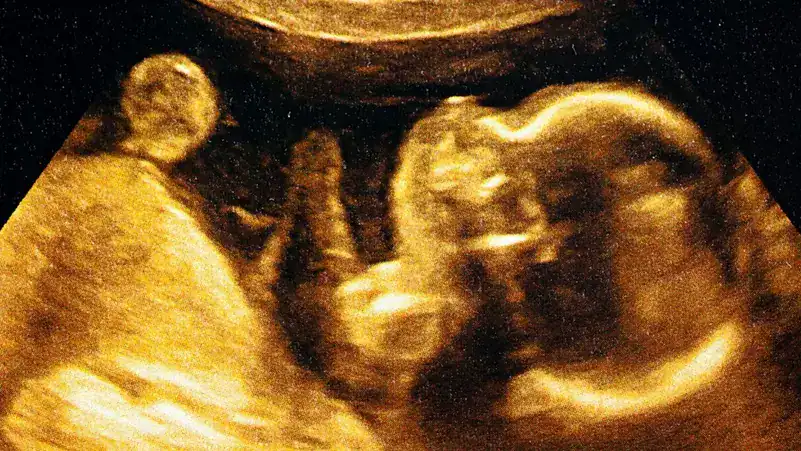

لطالما كان نمو الجنين داخل رحم الأم ظاهرة معقدة ومحورًا للعديد من الأبحاث العلمية، حيث يتداخل فيها علم الوراثة بعلم وظائف الأعضاء في منظومة بالغة الدقة. إن التفاعل بين الأم والجنين، وتحديدًا آليات حصول الجنين على المغذيات الأساسية لنموه وتطوره، يظل مجالًا غنيًا بالاكتشافات المتوالية. وفي هذا السياق، كشفت دراسة حديثة عن آلية مدهشة تغير فهمنا التقليدي لدور الجنين السلبي في هذه العملية، مؤكدة على قدرة الجنين على التحكم بنوعية المغذيات التي يستمدها من الأم.

في خطوة علمية رائدة، أعلن فريق من الباحثين في جامعة كامبريدج البريطانية، وفقًا لما نشرته بوابة السعودية، عن اكتشاف آلية فريدة تتيح للجنين التحكم بشكل مباشر في نوعية المغذيات التي يتلقاها من أمه خلال فترة الحمل. هذا الاكتشاف يعد إنجازًا مهمًا في مجالي علم الوراثة وعلم الأجنة، ويفتح آفاقًا جديدة لفهم التفاعلات المعقدة التي تحكم صحة الجنين وتطوره.